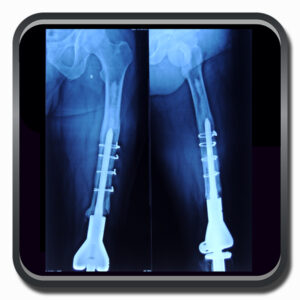

Algumas Cirurgias Complexas realizadas por profissionais da COFIB: